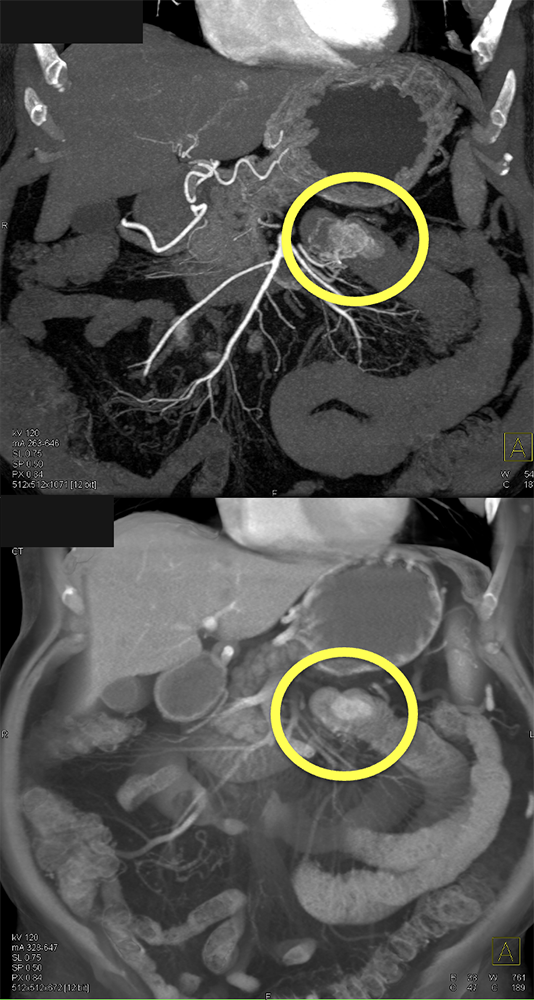

GIST Tumor Jejunum as the Cause of GI Bleeding ![]() |

![]() |

GI Bleed ![]() |